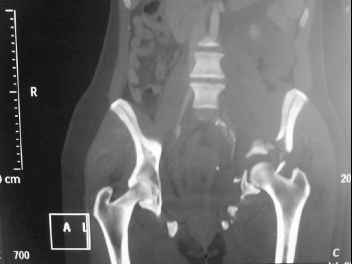

I'm posting this case on behalf of Dr. Pedro Caba, he is unable to post but able to read. 41 yo female , fall from 10 meters five days ago. Hemodynamically unstable on admission treated by angio and embolization and skeletal traction, with no external support. No associated injuries. Based on CT scan the pt has a both column fracture with conminuted dome and displaced anterior column and a sacral Denis 1 fracture with a displaced left ala. I think the best approach for the acetabular fracture is ilioinguinal with Smith-Petersen extension but don't know exactly the sequence . Will you start with the sacral fracture? Which technique? Thanks in advance Pedro Caba Unidad de Trauma Hospital 12 de Octubre Madrid Spain

The soft tissues are also in mild condition, buttock hematoma and probably a Morel-Lavalle. I send some more CT images. There are some conminution in the posterior column (I don’t have images now). The patient is scheduled for surgery next Monday. The plan is percutaneous sacral fixation and then ilioinguinal approach .